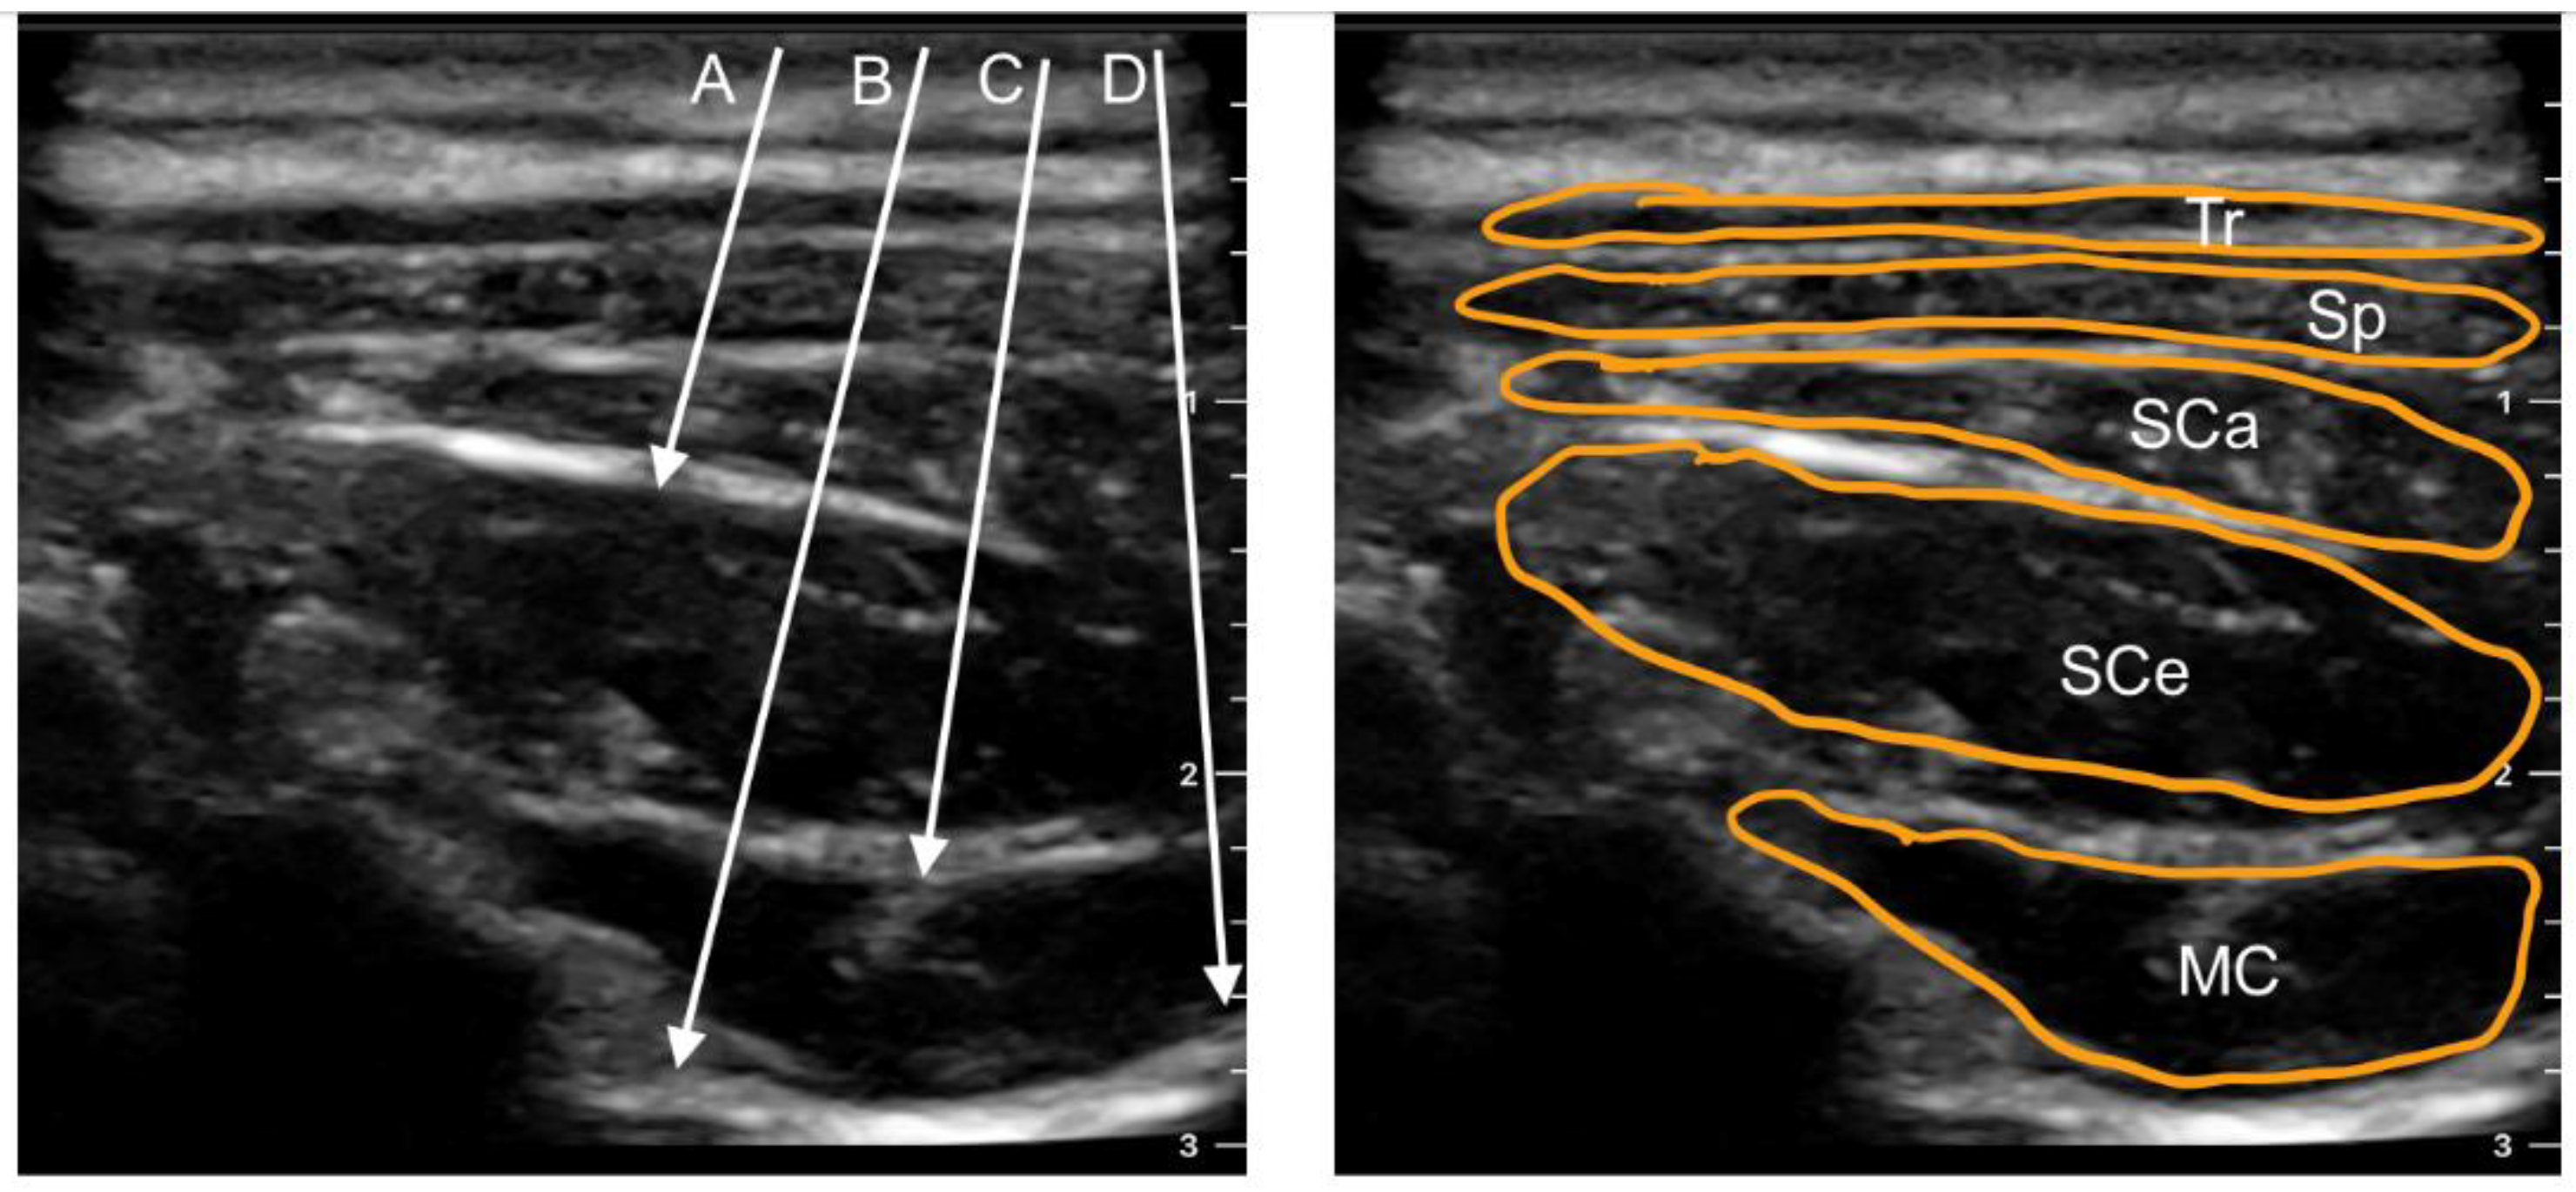

5.1. Multifidus Cervicis Plane Block (MCP)

5.2. Retrolaminar Cervical Block

5.3. Inter-Semispinal Plane Block (ISP)

6. Cervical Erector Spinae Plane Block